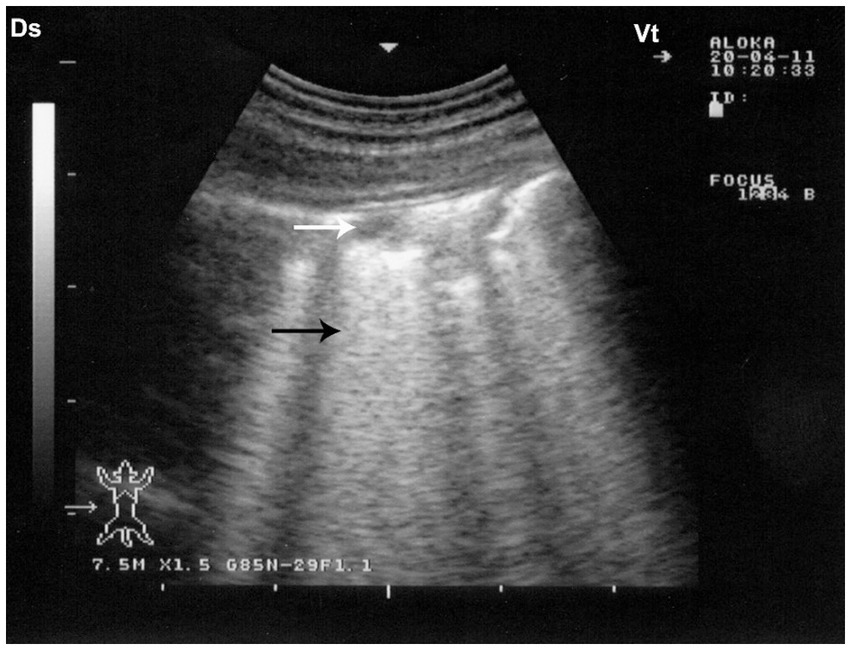

Figure 9. Sonographic findings in drenching pneumonia. The lung surface exhibits multiple small hypoechoic zones (white arrow) interpreted as superficial fluid alveolograms, along with characteristic comet-tail artifacts (black arrow), indicative of interstitial-alveolar pathology. Ds – Dorsal; Vt – Ventral [modified from Tharwat and Al-Sobayil (8)].